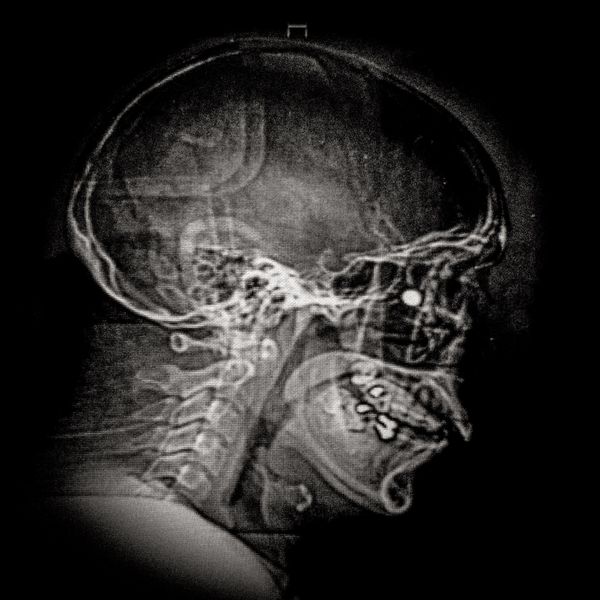

X ray showing the embedded pellet of an injured man during Santiago protests.

© Cristóbal Olivares - X ray showing the embedded pellet of an injured man during Santiago protests.